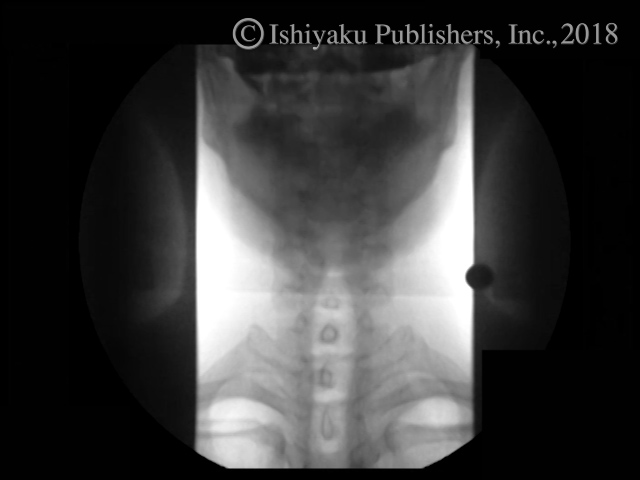

動画1 術前嚥下造影検査